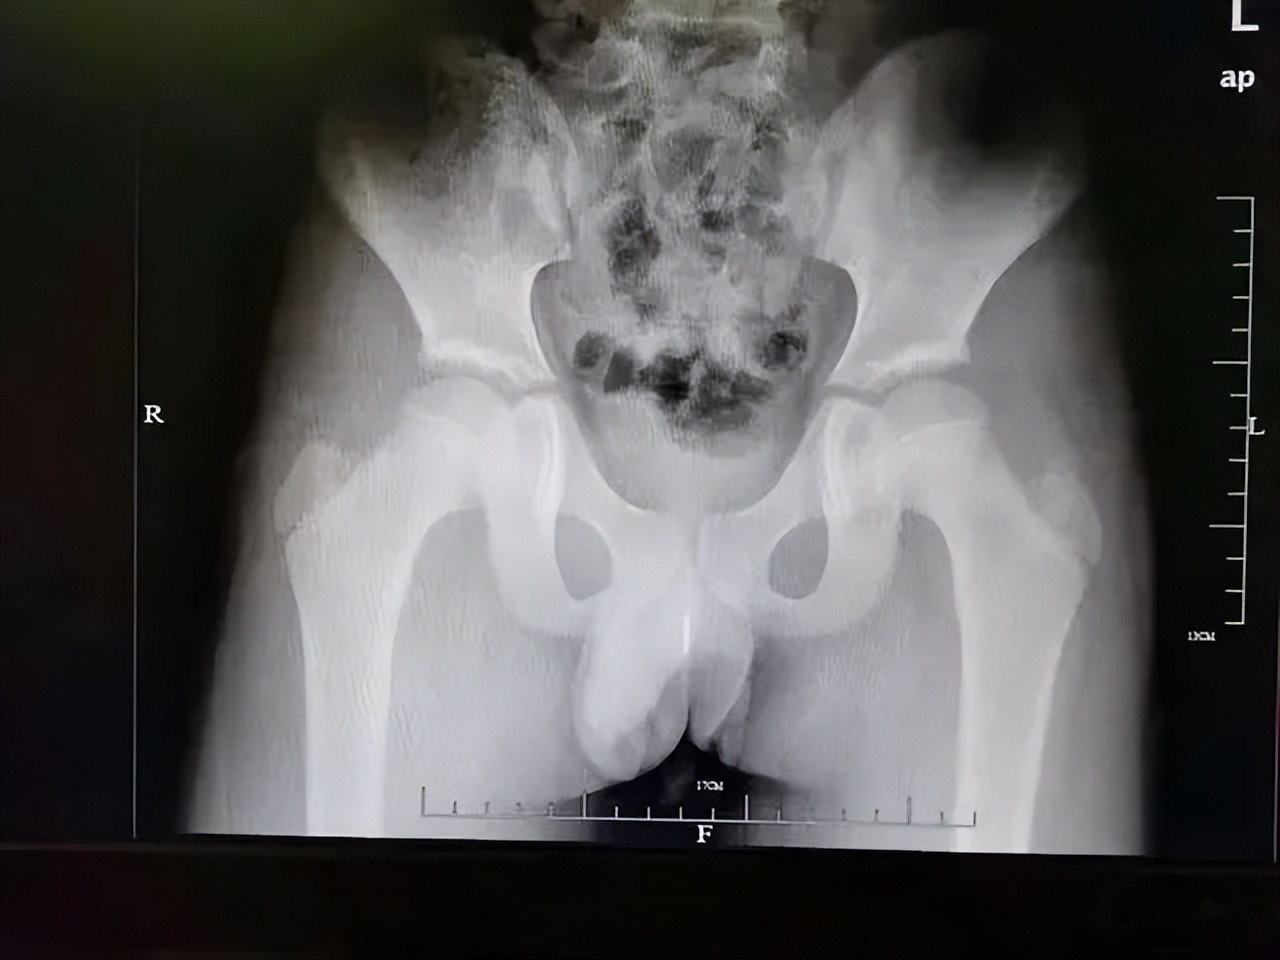

深圳一名13岁男孩,出于好奇往尿道里塞进186颗磁力球!

结果拍完片一看,医生都吓一大跳,孩子的膀胱里密密麻麻地全是磁力球。

这些磁力球全都粘在一起,根本排不出去,医生只能通过微创手术,将磁力球一颗一颗夹出来。